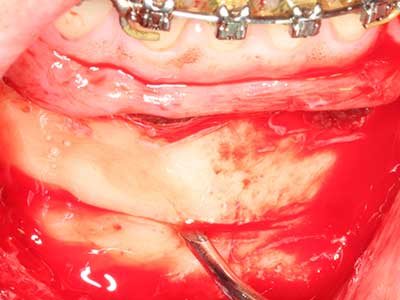

Si es preciso realizar intervenciones quirúrgicas en las que el hueso está en contacto directo con estructuras sensibles, como son los vasos sanguíneos o los nervios, los instrumentos rotativos presentan un enorme potencial de provocar lesiones iatrogénicas. Así, precisamente en la representación de nervios después de una lesión iatrogénica, o en el transcurso de la lateralización de un nervio para resecciones, reconstrucciones o incorporación de implantes, los equipos piezoeléctricos pueden resultar muy útiles para preparar la tapa ósea y retirar las partes de tejido duro cercanas al nervio (fig. 17-20). Por lo general, un ligero contacto del cordón nervioso con el inserto piezoeléctrico no tiene consecuencia alguna; ahora bien, un procedimiento poco cuidadoso con movimientos tipo sierra o piezas de trabajo sobre la base ósea aún existente puede provocar lesiones nerviosas temporales o incluso permanentes. Con todo, el riesgo de sufrir una lesión de este tipo se considera significativamente inferior que en los casos en los que se utilizan sierras y fresas (Pereira, Gealh et al. 2014).

Fig. 17: Tomografía computarizada de un osteoma de crecimiento progresivo ...

Fig. 17b: justo al lado del canal alveolar con irritación nerviosa (vista lateral y coronal).

Fig. 18: Preparación de una tapa cortical con la sierra ósea piezoeléctrica (Piezomed, W&H).

Fig. 19: Zona operada después de neurolisis y eliminación del osteomo.

Fig. 20: La tapa ósea extraída se readapta y se fija mediante un tornillo para osteosíntesis (KLS Martin, Tuttlingen).